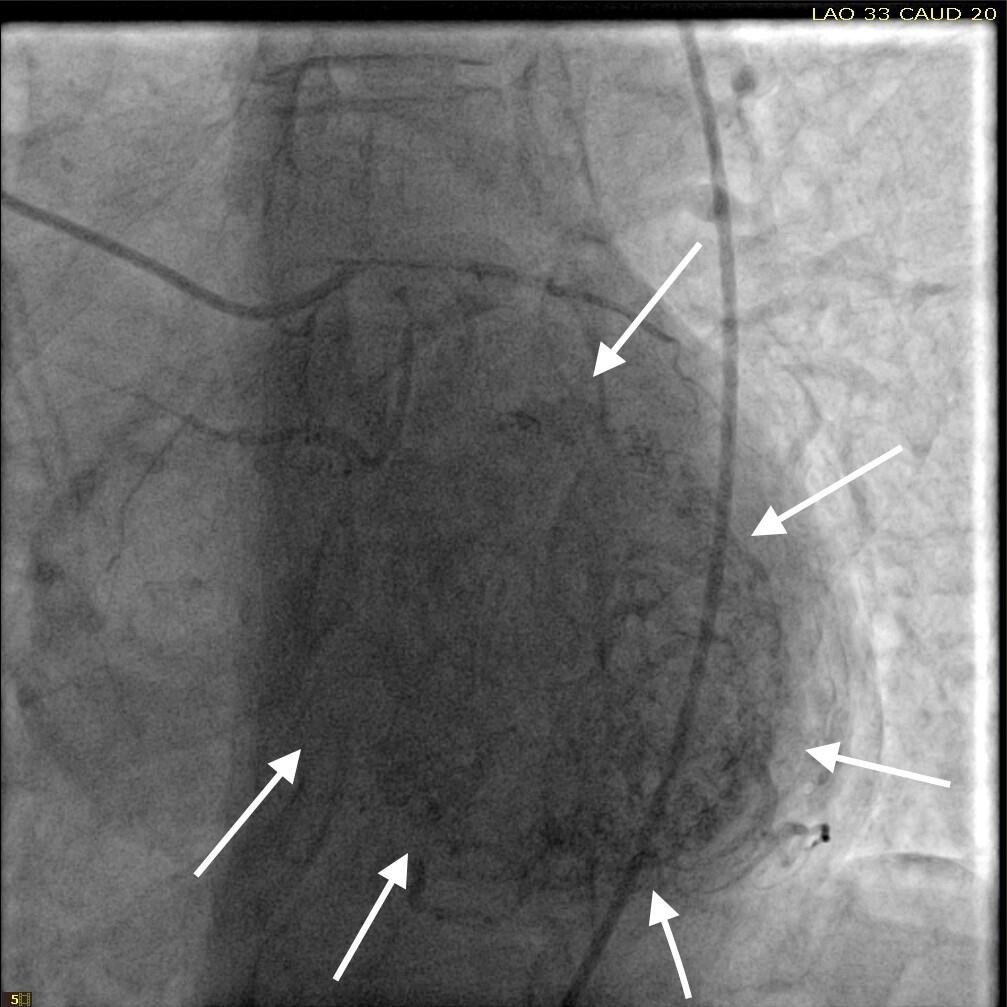

She was taken for a diagnostic left heart catheterization which showed mild to moderate disease in multiple coronary arteries with severe stenosis of a small caliber mid right sided Posterior Descending Artery (rPDA) not amenable to percutaneous intervention. The cardiac catheterization also revealed an extensive network of microfistulae forming communications between all three major coronary arterial branches (i.e., LAD, Right Coronary Artery [RCA], and Left Circumflex [LCx]) and the LV cavity (Figures 2, 3, and 4). This patient’s flow through her microfistulous communications was so brisk that a perfectly interpretable left ventriculogram was visualized with coronary angiographic imaging via a hand injection of contrast into the left coronary arterial system (Figures 3 and 4).

It was not possible to quantitate this patient’s amount of flow through her extensive thebesian venous network since it is generally extremely technically difficult to do so.7 However, it was obvious that this woman’s total thebesian venous flow far exceeded the upper limit of what is considered typical since her LV ejection fraction (normal being in the range of 54 - 74% in women) could easily be interpreted with a hand injection during left coronary artery angiography. On the second day after admission, complete 2D echocardiography was performed only showing moderate LV hypertrophy.